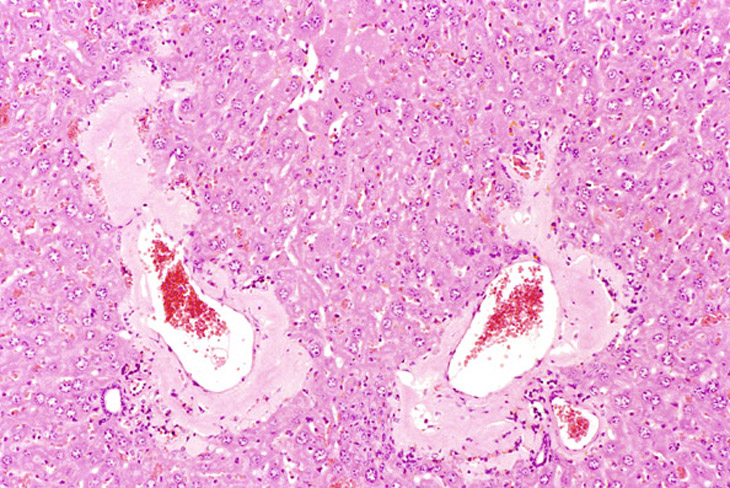

Amyloid deposition is rare in B6C3F1 mice but more common in the liver (and also the gallbladder) of CD-1 mice. It is usually located beneath the sinusoidal lining and in the wall of portal blood vessels. Amyloid deposition around blood vessels in the portal areas.